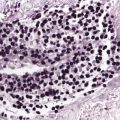

There are dense, diffuse lymphoid infiltrates within the entire dermis and subcutaneous fat (Fig. 13.9). Involvement of the epidermis by large neoplastic cells may be observed rarely, indistinguishable from Darier’s nests (Pautrier’s microabscesses) (Fig. 13.10). Rare cases may even show band-like infiltrates in the superficial and mid-dermis, simulating the histopathologic pattern of mycosis fungoides (see Teaching case 13.1). Sparse perivascular collections of large cells may be observed in early lesions and may be the source of diagnostic problems (Fig. 13.11). Angiocentricity is an uncommon finding (Fig. 13.12) [17]. The neoplastic infiltrate consists predominantly of large cells with round nuclei (immunoblasts and centroblasts) (Fig. 13.13). Reactive small lymphocytes are usually only sparse. Mitoses are frequent.